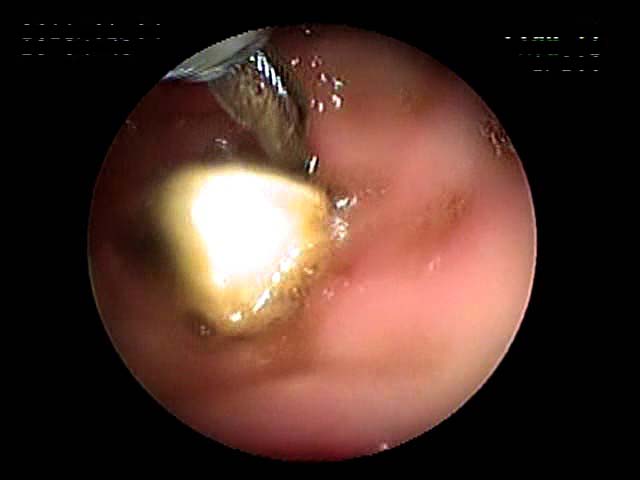

数日前、近隣の動物病院からのご紹介で、お子さまのミートボールに楊枝(プラスチック製、キリンの形)が刺さった状態で丸飲みした5kgのワンちゃんが来院されました。2日経っても出てこなく、やはり嘔吐が見られました。今回のケースは、4日後に遠方のご自宅に戻られるという期限がついていました。ということは試験開腹手術はできるだけ避けることに・・・というプレッシャーがのしかかります(笑)。

内視鏡を駆使してなんとか掴み出すことができました。今回の難関は、掴む所がない可能性でした。よく内視鏡下で見たところ、キリンの角が細かったため唯一のつかみ所でした。うまくいきました。(実は、ご来院の際に見本として現物をお持ち頂いていました。しかし、その際はワンちゃんでしてつかみ所が全くありませんでした・・・キリンさんでよかったです~)

内視鏡の使い方はいろいろあります。異物摘出、食べ物詰まりの胃内への押し込み、肉眼的観察、バイオプシー(病理検査)、胃瘻チューブ形成 など、まだまだ可能性を秘めています。その技量を問われる異物摘出。幸いいろいろな経験に巡り会いましたので、これからもご紹介したいと思います。これを見ていただいた方にペットの誤飲の教訓になればとの気持ちを込めて。

キリンの楊枝が食道内 実際とれたあとの写真

まで来ている様子